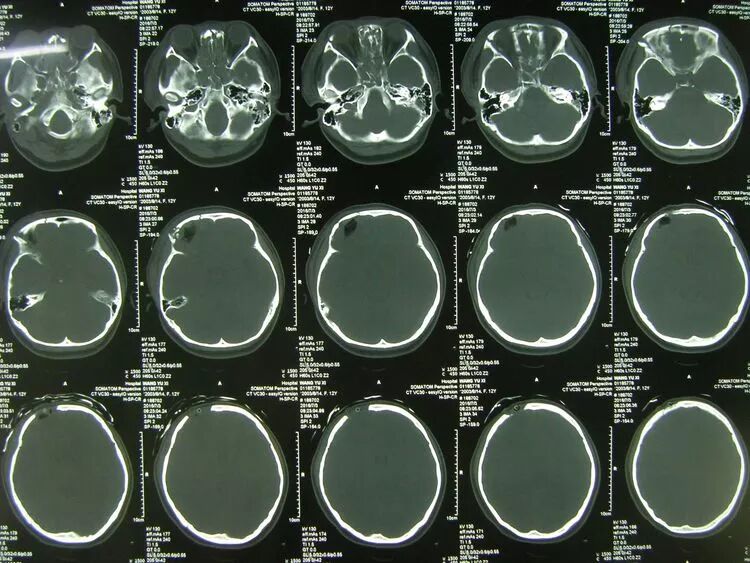

骨窗片显示额骨及颅底骨粉碎骨折

术后1天CT复查,止血减压良好,基底池清晰,中线居中,患儿神志转清。

术后骨窗片